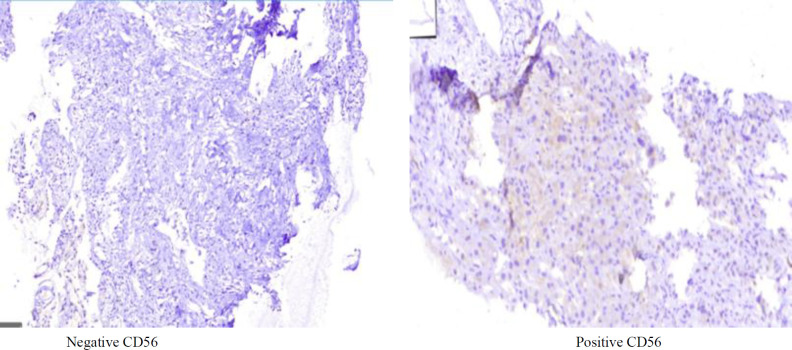

Results: Of the 81 specimens, the mean age in the case and control groups was 57.33 ± 11.99 and 44.7 ± 16.69 years, respectively, and 51 (63%) samples were obtained from male patients. We found that 39.5% had grade III p53 expression, 13.5% had grade II p53 expression, 41.9% had grade III CEA expression, and 9.8% had grade II CEA expression. Additionally, 17.3% were positive for CD56 expression, and 7.4% showed SMAD4 loss. There were significant associations between the expression of CEA (79.6%) and p53 (74%) in the CCA group (p-value < 0.05). However, SMAD4 loss and CD56 expression were not statistically significant.

Conclusion: Expression of CEA and p53 based on IHC staining is associated with the occurrence of CCA. However, SMAD4 and CD56 were not significantly associated with CCA. Further survival analysis and sensitivity and specificity assessments are needed to obtain more comprehensive results.